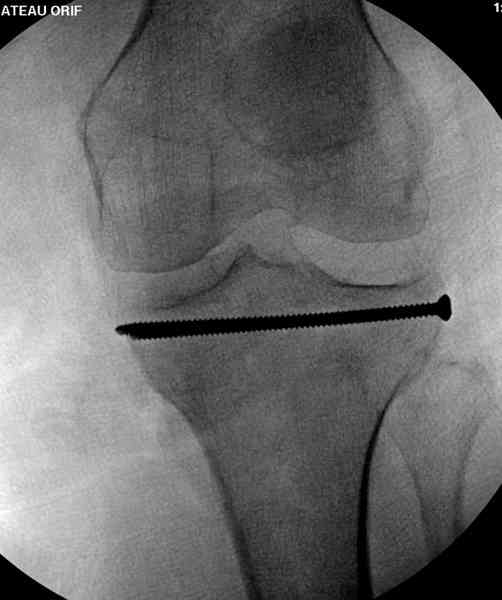

Нет, малоберцовый внизу, фиксацию проводим на верхнем эпифизе, где твердая кость. Задача состоит

в том, чтобы создать арматуру из нескольких проведенных шурупов на эпифизе.

Медиально, обычно на протовоположной

строне, делается окно в кортикальном слое, кривым забойником под рентгеном поднимается импрессия.

Это техника применяется, когда имеется

центральная импрессия, а при ипрессии с краевым переломом - после приподнимания импрессии опорная (Butress) пластина, как на снимке.